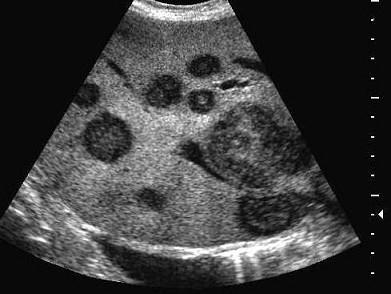

问题 女性,59岁,右上腹痛。腹胀1周。病人于1991年因直肠癌行手术治疗。如果拟诊为继发性肝癌,超声表现错误的是?(?)

选项 A.肝内单个强回声结节 B.多发的强回声结节 C.病灶呈多样性 D.病灶彩色血流不明显 E.病灶边界清楚,周围有声晕,呈牛眼征

答案 A